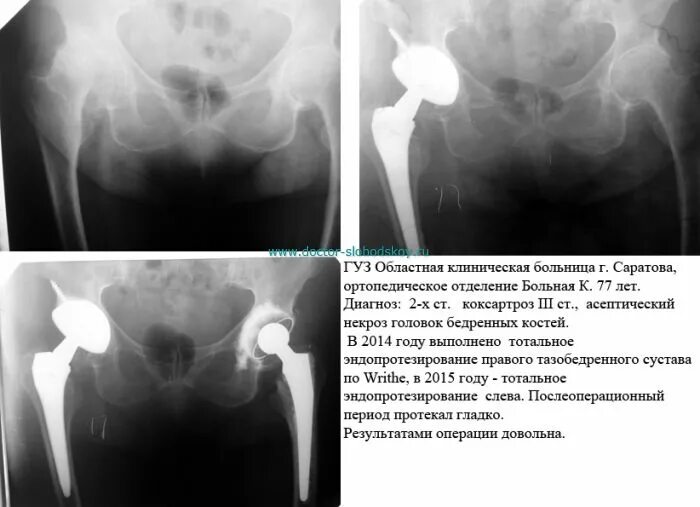

Некроз головки тазобедренного сустава 2